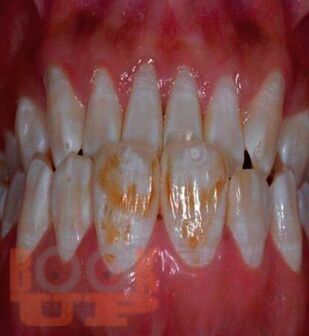

Ce manuel a été élaboré conformément au programme de travail «Anatomie pathologique» et est destiné au développement des compétences professionnelles des étudiants de 2e année de la Faculté de médecine dentaire dans la discipline «Anatomie pathologique» dans la spécialité 31.05.03 Dentisterie. Le manuel comprend plusieurs chapitres, dont une description de la structure normale et de l'anatomie pathologique des maladies des organes dentaires en français. Le manuel est équipé d'un grand nombre de photographies, le matériel est présenté à un niveau théorique moderne.

Данное учебное пособие разработано в соответствии с рабочей программой «Патологическая анатомия» и предназначено для освоения профессиональных компетенций студентами 2 курса стоматологического факультета по дисциплине «Патологическая анатомия» по специальности 31.05.03 Стоматология. Учебное пособие состоит из нескольких глав, включая описание нормального строения и патологической анатомии заболеваний органов зубочелюстной области на французском языке.

Пособие оснащено большим количеством фотографий, материал излагается на современном теоретическом уровне.